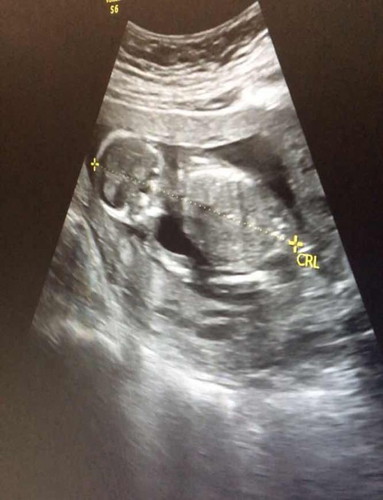

1มีนาคะ ปวดเมื่อยทั้งตัวคะ ลูกชอบดิ้นแรงตอนกลางคืน กลางวันจะเงียบหน่อยคะ ซาวครั้งก่อนหมอบอกน้ำหนักเด็ก400กรัม ไม่รู้เพศ เพราะเด็กแอบอยุ่555